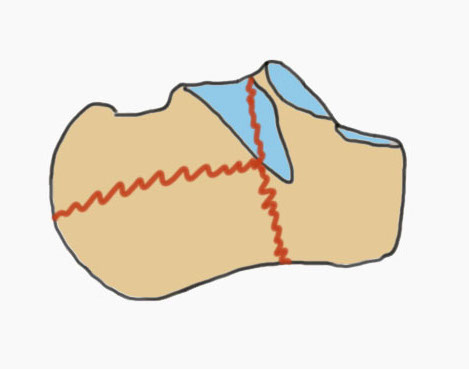

Fracture patterns

| Primary fracture line | Secondary fracture lines |

|---|---|

|

Lateral process of talus driven into crucial angle - starts at lateral wall near tarsal sinus - passes obliquely across posterior facet - exits at medial wall posterior to sustentaculum tali |

Passes immediately behind the posterior facet of the subtalar joint - exits posterior to posterior facet & anterior to tendoachilles insertion - creates thalamic portion containing posterior facet |

Common fracture fragments

| Sustenacular | Superolateral | Lateral wall | Posterior tuberosity |

|---|---|---|---|

| Superomedial |

Lateral fragment of posterior facet

|

Tongue fracture | |

| Attached to talus by deltoid ligament | Thalamic fragement | Secondary fracture line exits below tendoachilles |